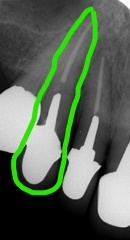

徐々に歯槽骨ももろくなり、歯周病や歯を失うリスクも高まります。

プロテタイトは、骨そのものです。(視覚的にも海綿骨とそっくりです)

骨に良い栄養を取り(骨ケア)、姿勢を正してよく嚙むことことは、下顎骨に刺激が加わり丈夫に(マウスケア)、さらに、